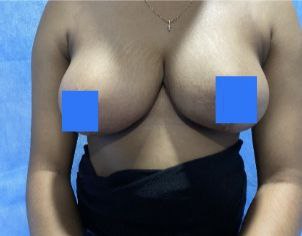

Cosmetic

BREAST REDUCTION